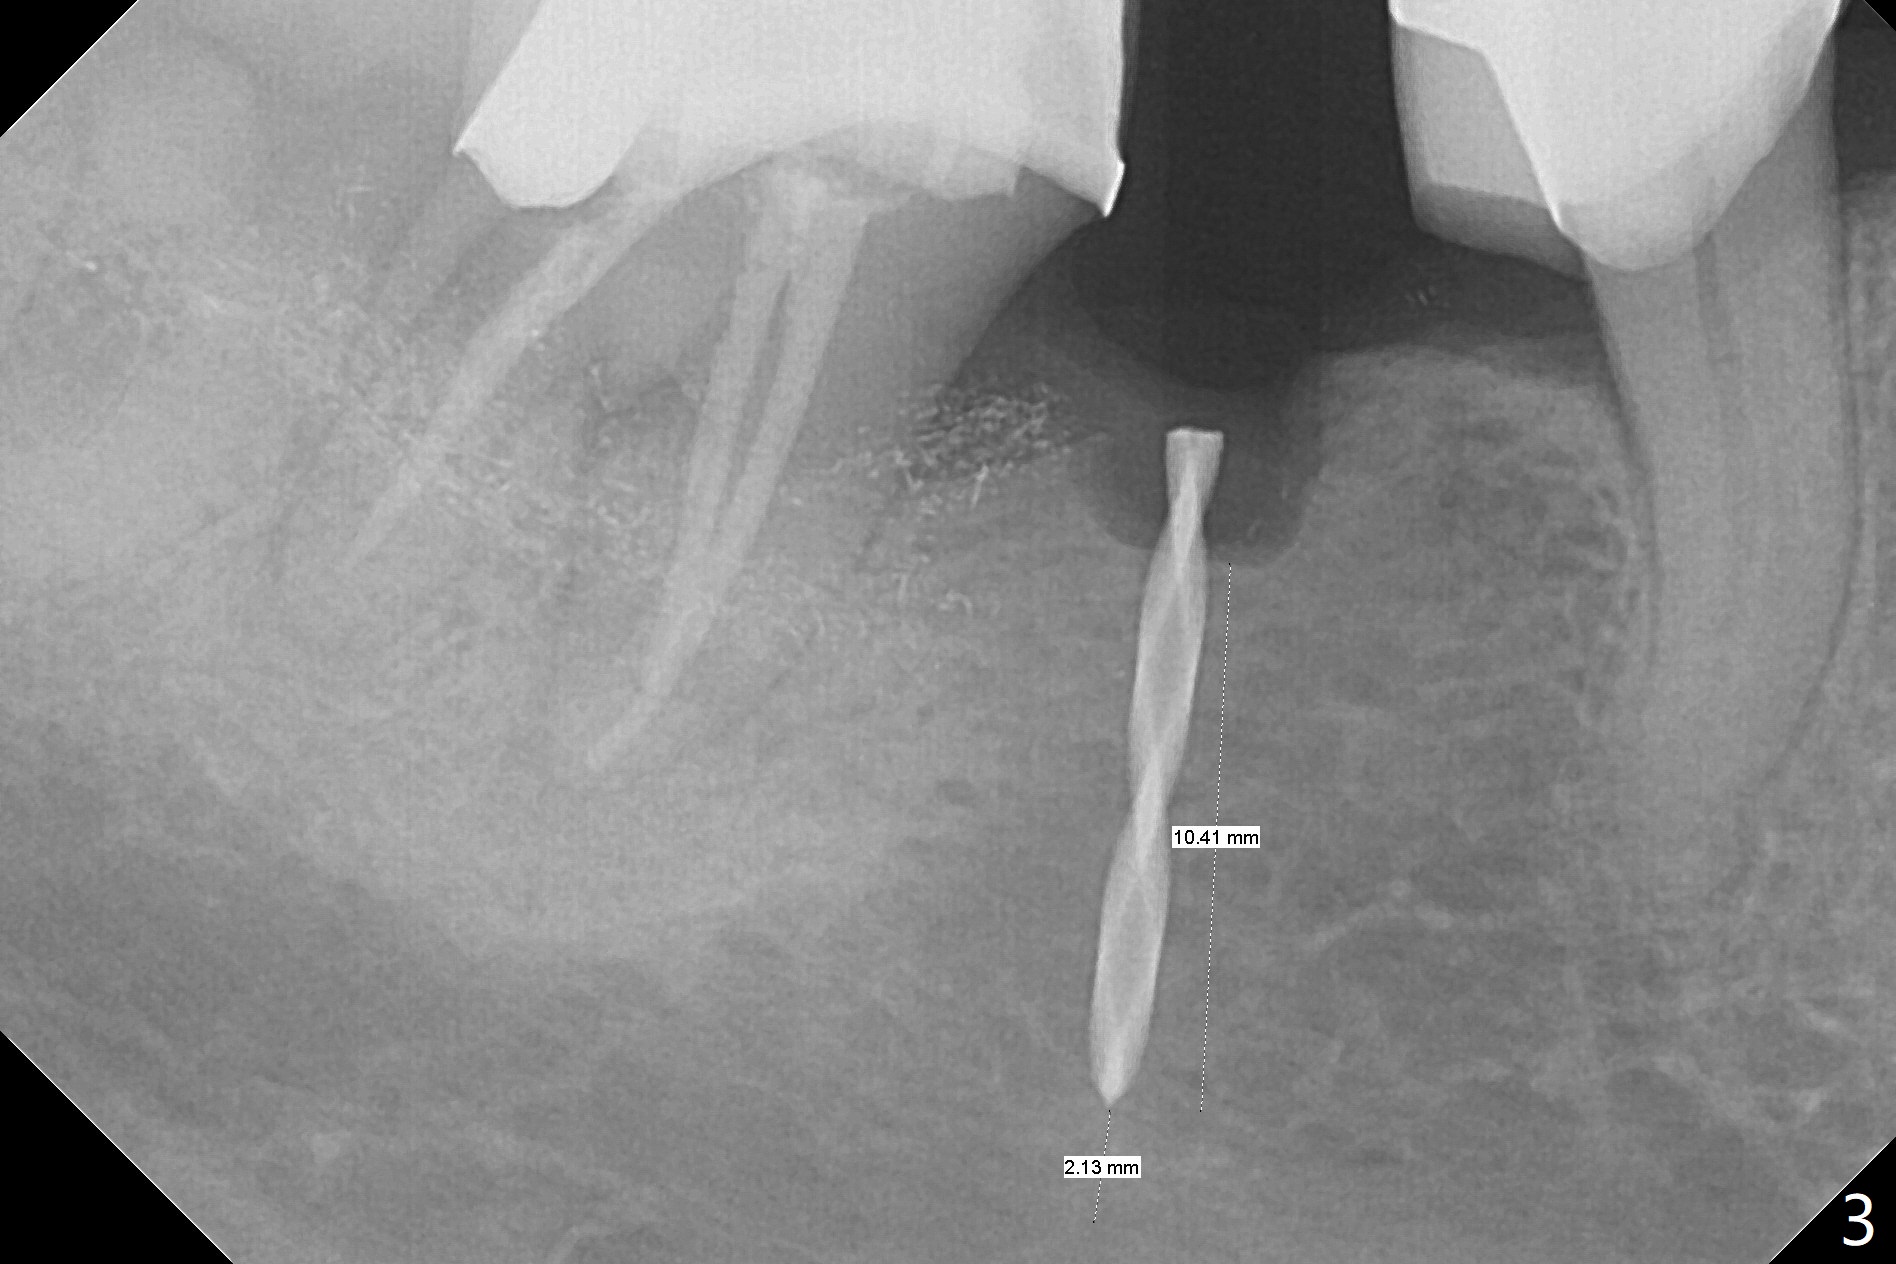

There is a space underneath the pontic at #30 (Fig.1 *), the basis for food impaction. After sectioning between the pontic and the posterior retainer, the pontic is removed from the anterior retainer with an attachment (Fig.2 *). The initial depth of osteotomy is 10 mm following ridge top reduction (Fig.3). A 3x10(4) mm 1-piece implant is placed with >50 Ncm; to reduce possibility of crown dislodgement from the implant, the retainers will be kept with modification of the proximal surfaces as shown by curved lines in Fig.4. Periodontal dressing is applied after suturing. There is no postop paresthesia. The periodontal dressing remains in place 2 weeks postop because of engagement into the attachment slot and undercuts (Fig.5). The patient returns 3 months postop; after minor contour adjustment (Fig.6 red curved line), impression is taken. The permanent crown is temporarily cemented (3.5 months postop) in case of food impaction due to the distal overhang of the tooth #29 (Fig.7). In fact the patient returns 4.5 months post cementation with right TMD (muscle relaxant prescribed) and food impaction, although there is no bone resorption (Fig.8,9). It appears that the crown at #29 needs to be redone, while porcelain will be added to the mesial surface of the one at #30 (Fig.10 red lines). In fact the crown at #30 is redone because of loose proximal contact with #31; there is no bone resorption 13 months post cementation (Fig.11). Bone resorption remains unnoticeable 28 months post cementation (Fig.12,13).